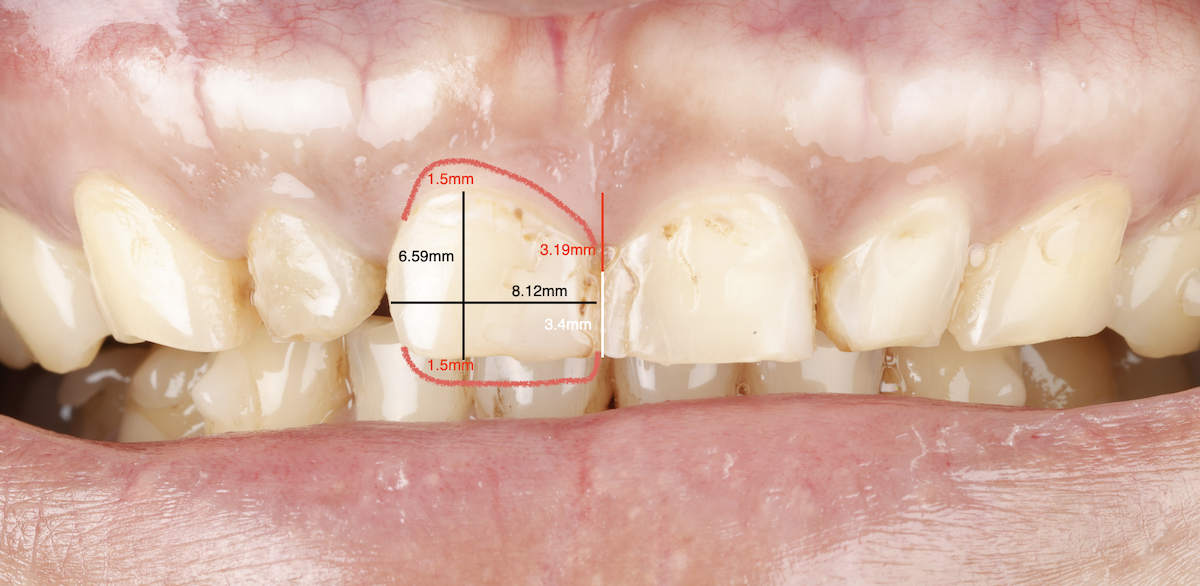

🔼 蒔美引進 DSD 微笑設計系統,讓患者在假牙製作前預覽未來笑容樣貌。再由數位牙體技術師同步製作臨時假牙,讓患者在實際試戴過程中,提前感受理想笑容的美觀與舒適,並根據李先生主觀感受進行微調,找到最終的完美方案。

Smile Introduces the DSD Smile Design System, Letting Patients Preview Their Future Smile. Digital dental technicians then create temporary prosthetics, allowing patients to trial their ideal smile and comfort. Adjustments are made based on Mr. Li’s feedback to achieve the final, perfected result.

在蒔美牙醫,李先生的全口重建不是倉促開始,而是從一份縝密的「終點藍圖」展開。薛聖儒醫師與陳延維教授聯手合作,透過多次遠端討論,從最終的微笑曲線到咬合高度,一再確認每個細節。

At Smile, Mr. Li’s full-mouth reconstruction didn’t start hastily—it began with a carefully crafted “end-point blueprint.” Dr. Xue and Dr. Chen collaborated over multiple remote discussions, reviewing every detail from the final smile curve to bite height.